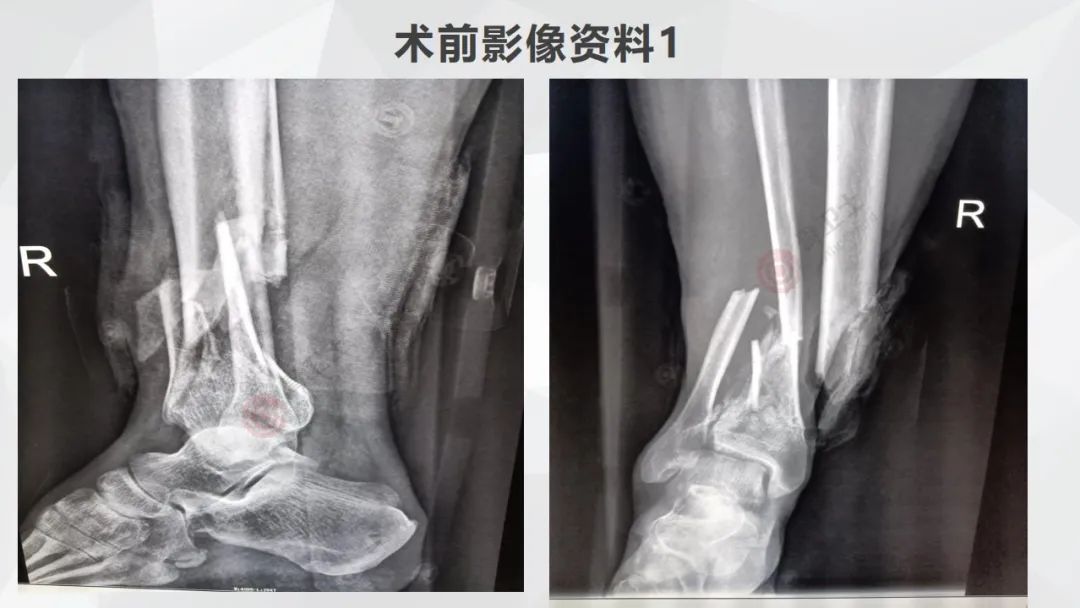

图片基本情况:患者,男,54岁,在家干活时从楼梯上摔伤,伤后感右小腿及右踝部疼痛,呈持续性刺痛,右踝部活动障碍,伴伤口流血,无昏迷,门诊予以伤口止血,予以右小腿支具外固定后转入骨科。

专科检查:右小腿可见外固定支具,右胫骨下段内侧可见长约4.5cm伤口,伤口渗血,伤口表面及周围少许泥沙,胫骨外露,可及骨擦感,右踝关节活动受限,踝关节无明显肿胀,足背动脉搏动有力,足背感觉正常,余肢肌力5级,感觉、活动正常。

辅助检查:胸部CT、右胫腓骨+右踝部CT重建示右侧胫腓骨下段粉碎性骨折伴周围软组织挫裂伤,胸部CT平扫未见明显异常。右胫腓骨+右踝关节DR示右侧胫腓骨下段粉碎性骨折并局部软组织挫裂伤,右腓骨头骨折。心电图未见明显异常。

640.jpg

▲患者术前影像